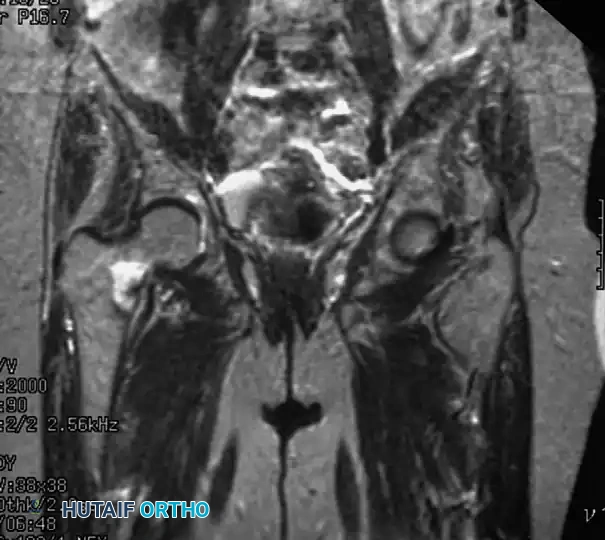

In cases where the clinical suspicion for a hip fracture is high but plain radiographs are equivocal, advanced imaging is mandatory.

Fig. 52-1: (A) Nondisplaced intertrochanteric fracture not visible on an initial AP radiograph. (B) The same fracture clearly identified on a T1-weighted MRI, demonstrating a hypointense fracture line.

- Magnetic Resonance Imaging (MRI): T1-weighted MRI is the gold standard for occult hip fractures. Studies by Quinn and McCarthy demonstrated that MRI is 100% sensitive and specific for identifying radiographically occult fractures.

- Bone Scintigraphy: Traditionally considered unreliable within the first 48-72 hours, modern studies (Holder et al.) have shown a 93% sensitivity for bone scans regardless of the time from injury, making it a viable alternative if MRI is contraindicated.